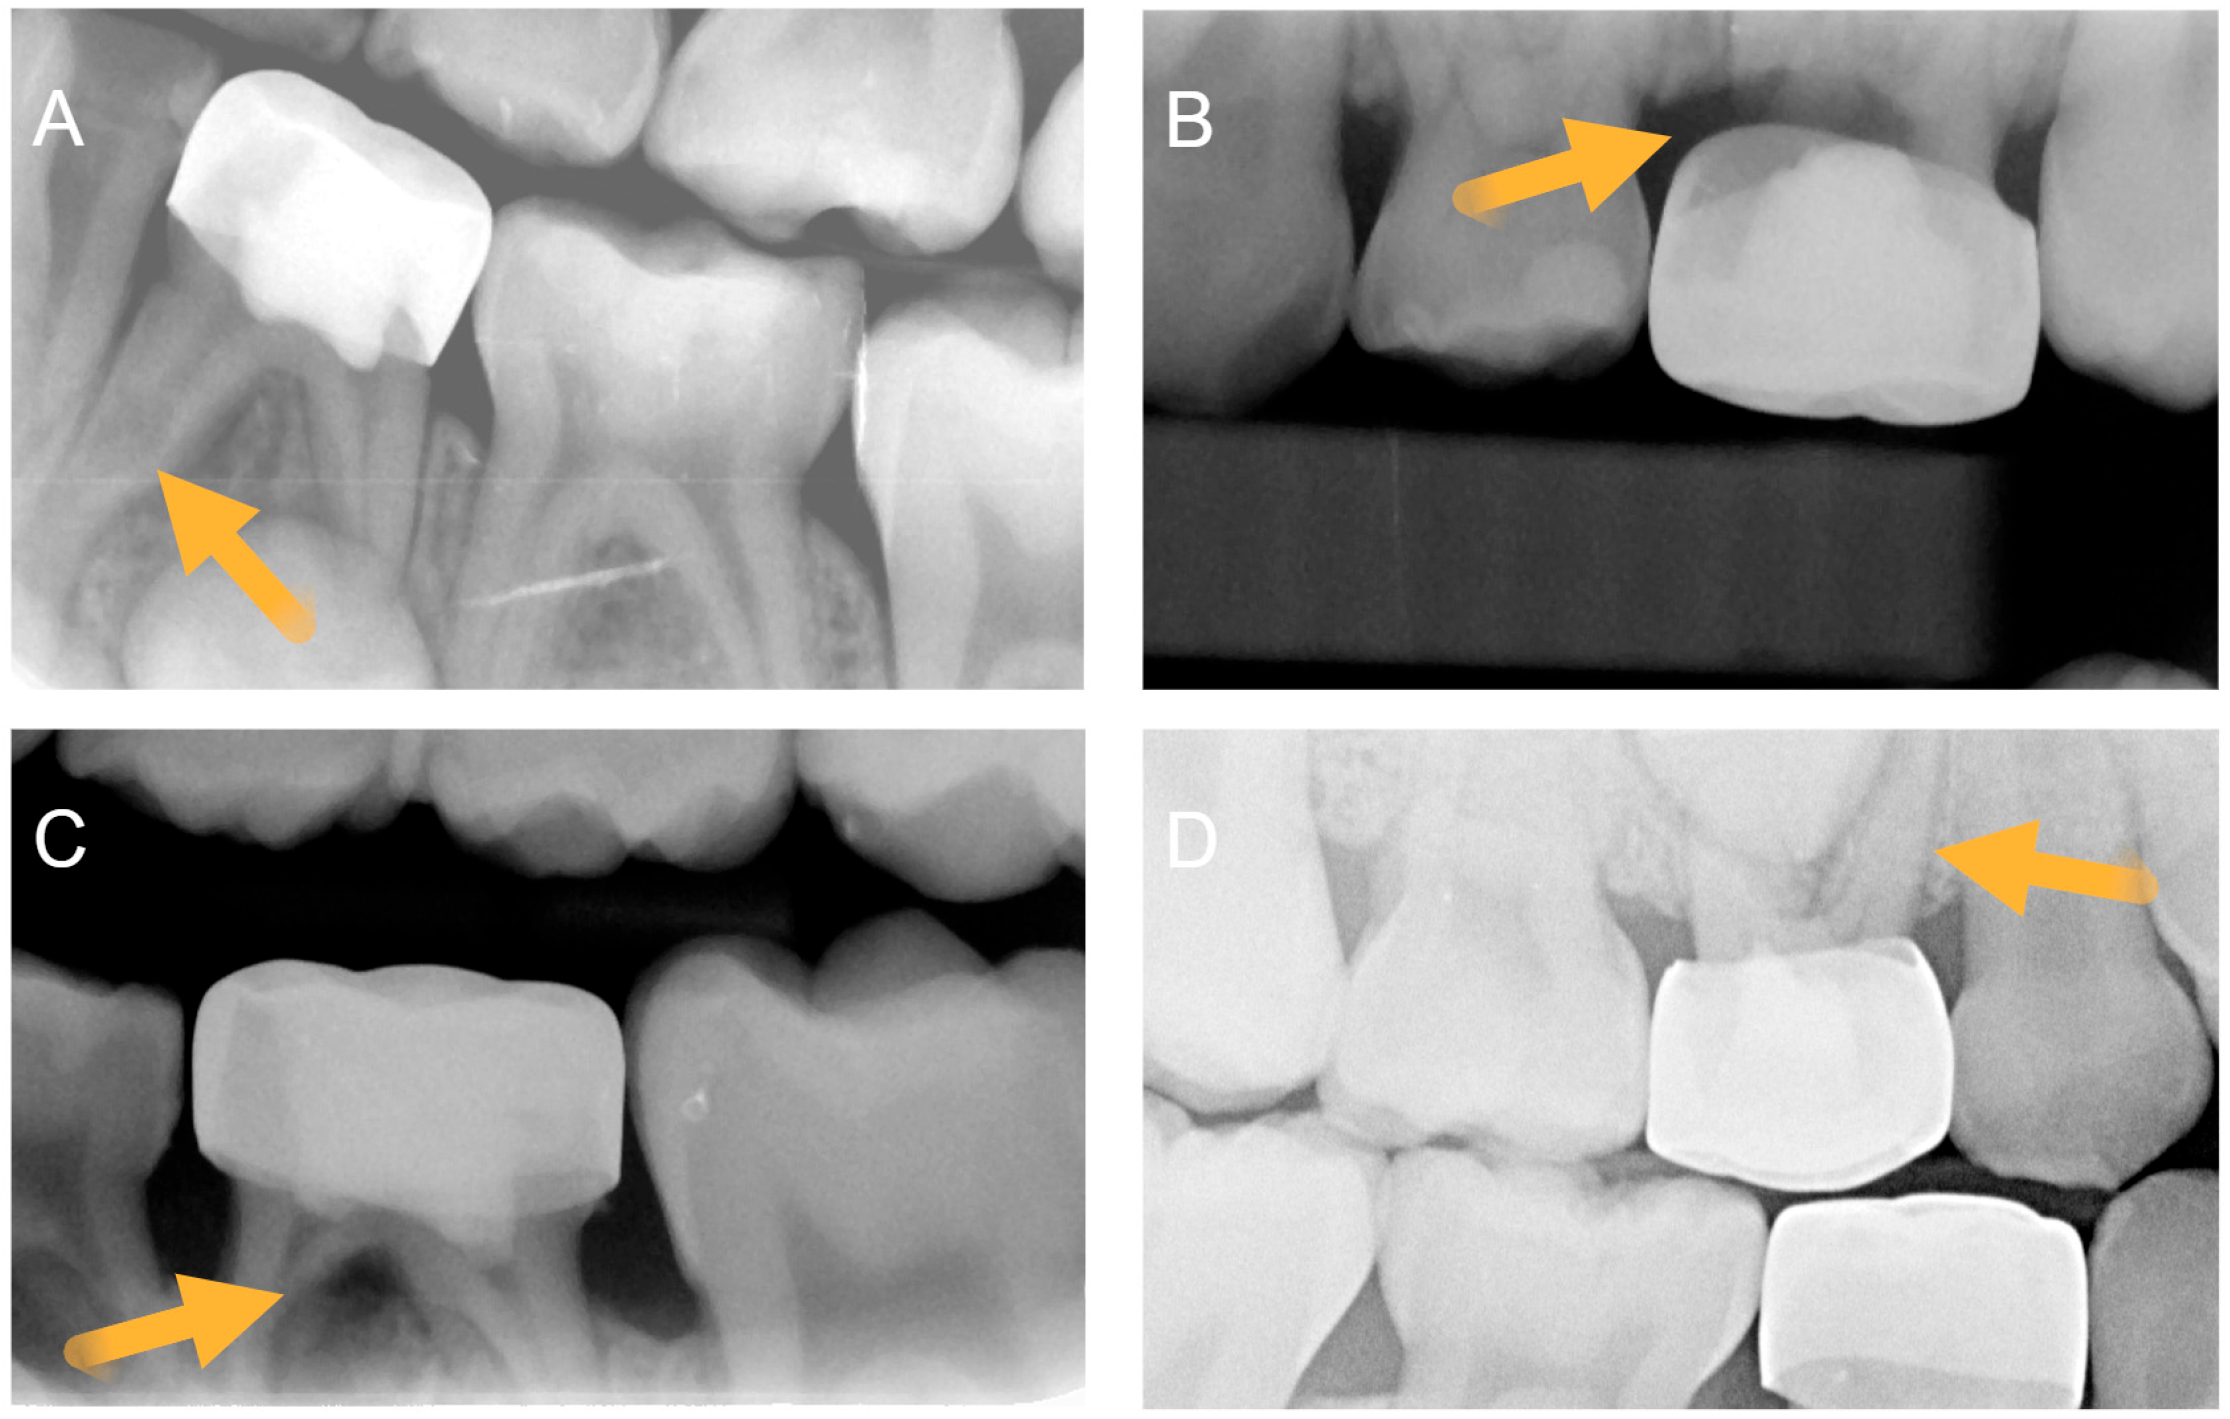

Intra-examiner agreement measurements (weighted Kappa) coefficient for the pre-op calibration of caries extending below the CEJ was 0.69, and post-op calibration dataset for evaluating furcation radiolucency was 0.74. For the main post-pulpotomy assessment, the blinded reviewer assessed the presence of internal root resorption (IRR), perforating IRR (IRR_P), and furcal radiolucency (FRL) as radiographic signs of pathosis (Figure 1). After organizing the blinded review into the two treatment groups, all signs of pathosis were observed more frequently in Group 1 than in Group 2 (Table 2). A total of 20 teeth (48.8%) in Group 1 eventually developed at least one form of radiographic pathosis, with 4 having multiple pathoses. For Group 2, a total of 8 teeth (23.5%) developed one form of radiographic pathosis. Slightly over half of all treated teeth in both groups eventually developed signs of pulp canal calcification (PCC), which was assessed as a vital, non-pathological finding.

Figure 1.

Post-pulpotomy radiographic assessment of (A) internal root resorption (IRR), (B) perforating IRR (IRR_P), and (C) furcal radiolucency (FRL). RR, IRR_P, and FRL were defined as signs of radiographic pathosis. (D) assessment of pulp canal calcification (PCC) that was defined as a non-pathological process. Arrows highlight representative conditions described.